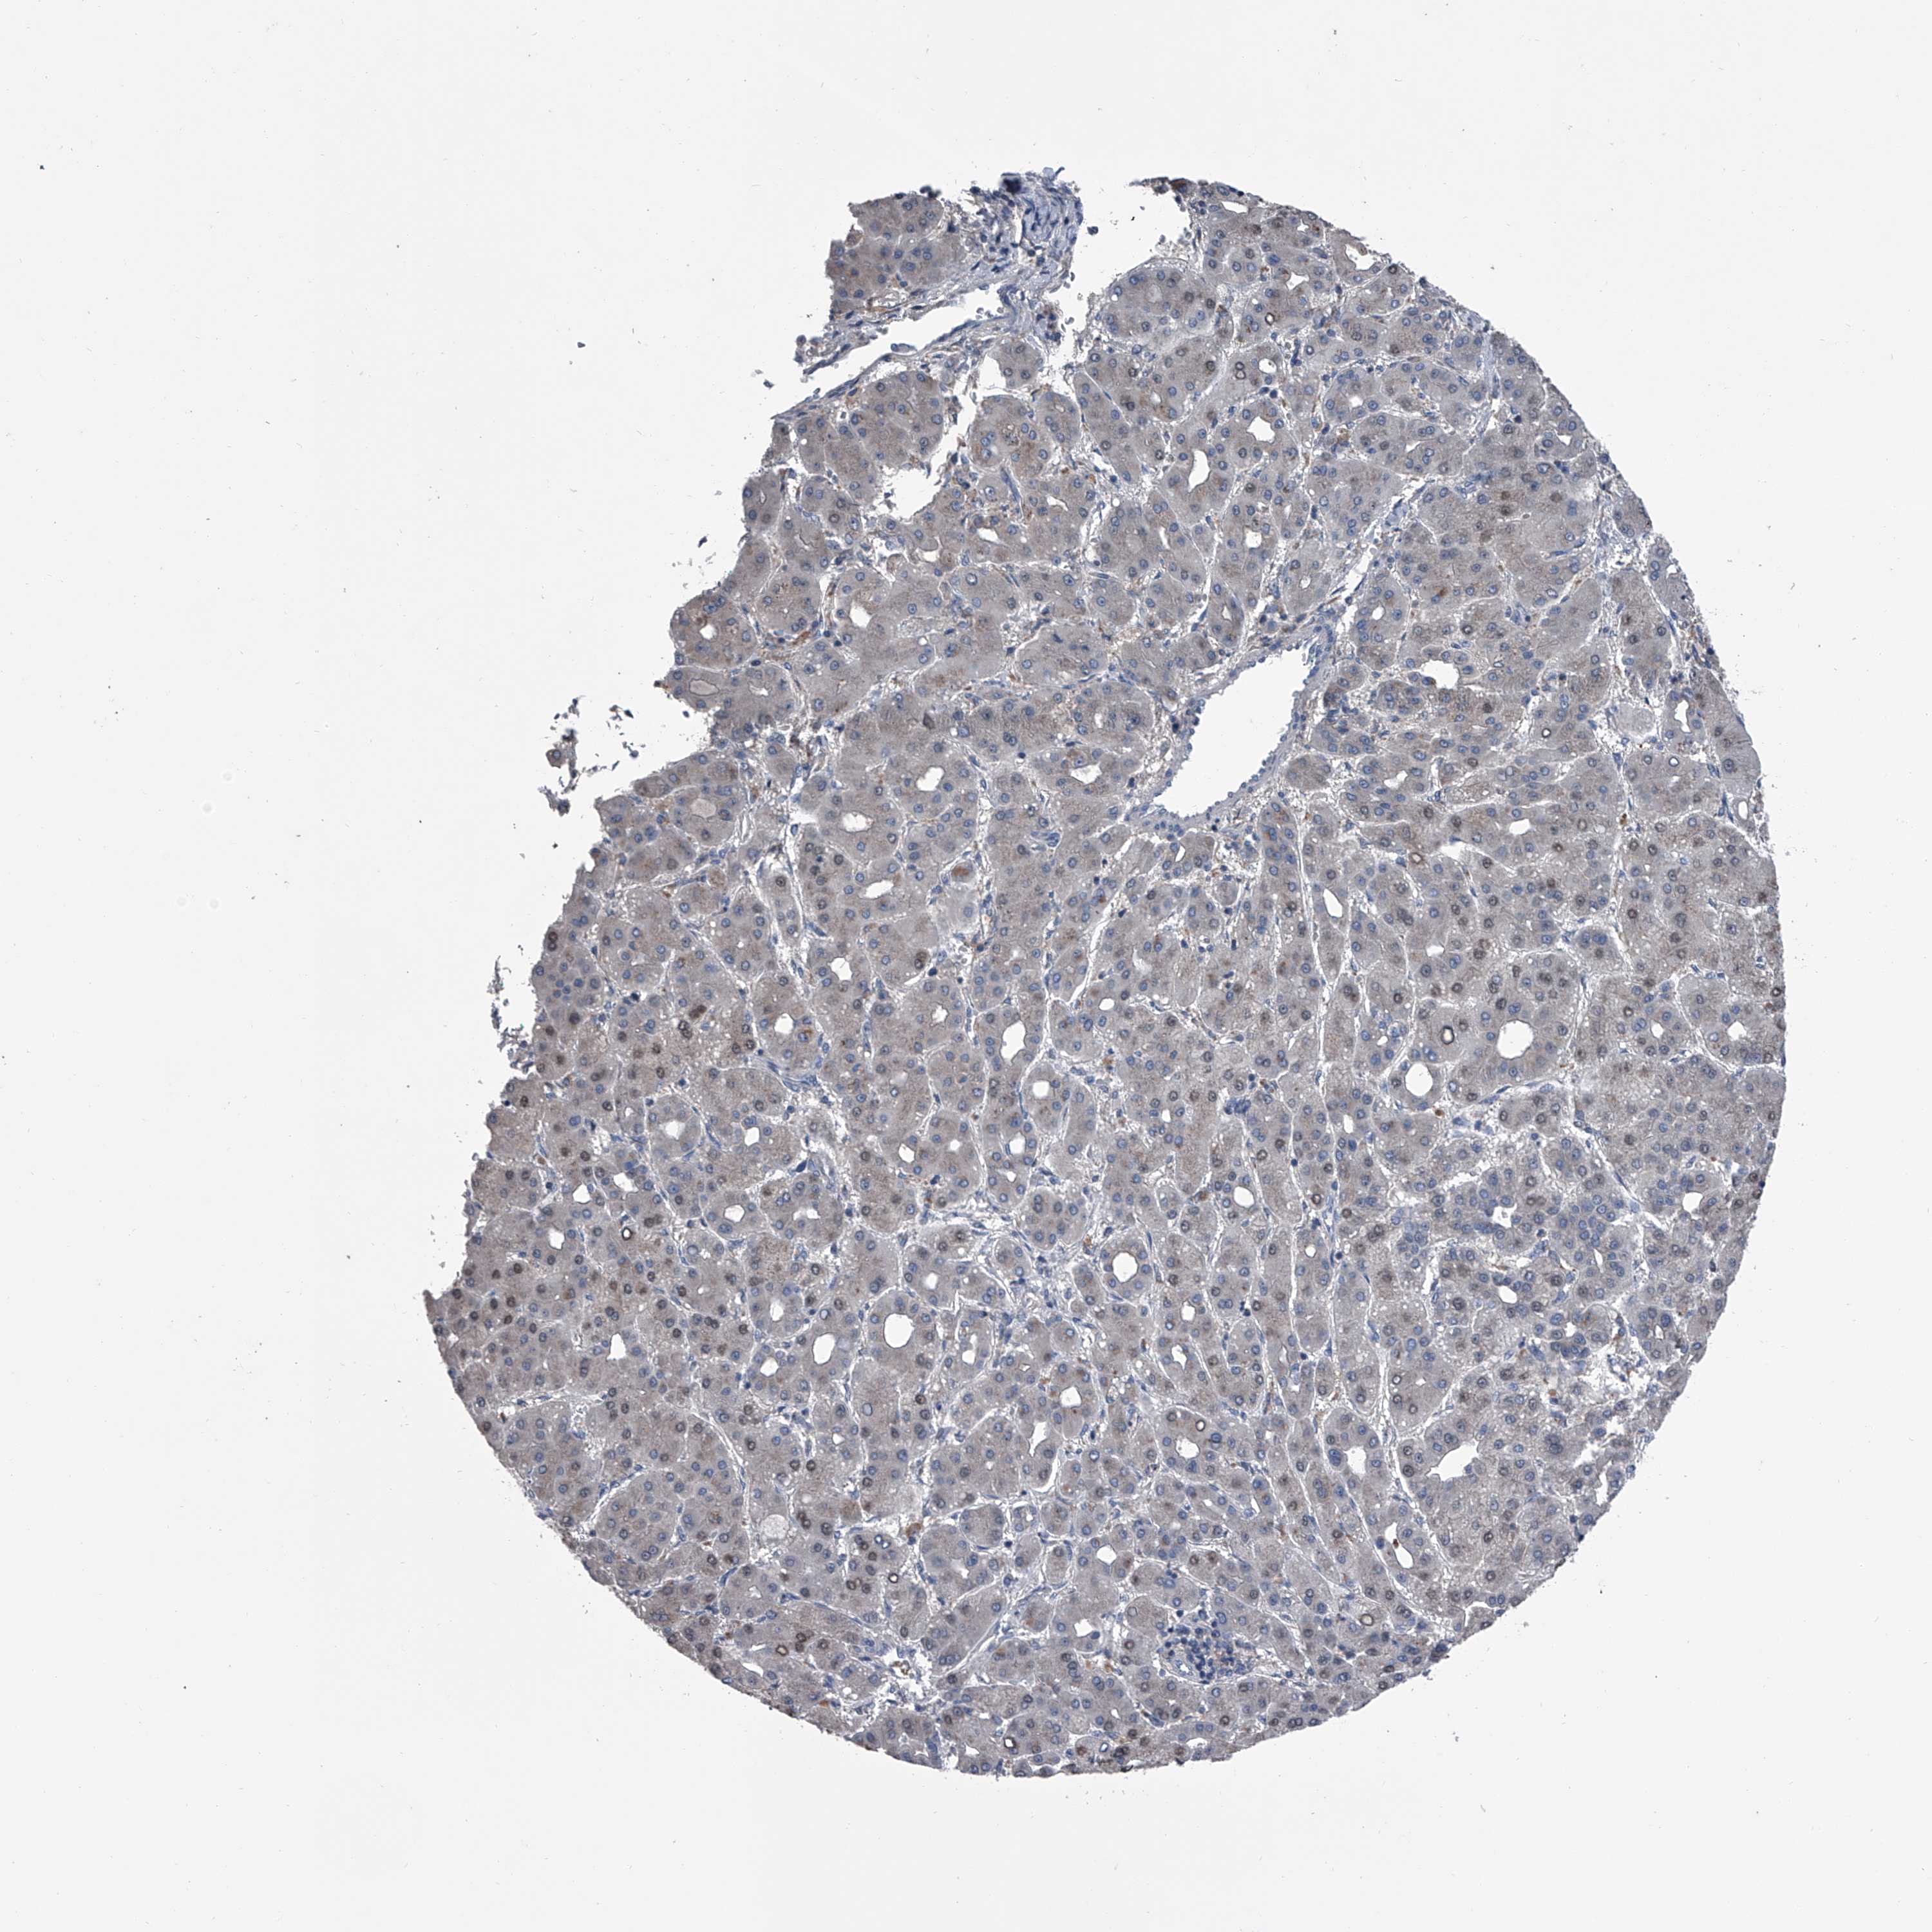

LIVER CANCER - Protein expressioni

A mouse-over function shows sample information and annotation data. Click on an image to view it in a full screen mode. Samples can be filtered based on level of antibody staining by selecting one or several of the following categories: high, medium, low and not detected. The assay and annotation is described here.

Note that samples used for immunohistochemistry by the Human Protein Atlas do not correspond to samples in the TCGA dataset.

Antibody stainingi

Antibody staining in the annotated cell types in the current human tissue is reported as not detected, low, medium, or high, based on conventional immunohistochemistry profiling in selected tissues. This score is based on the combination of the staining intensity and fraction of stained cells.

Each image is clickable and will lead to virtual microscopy that enables deeper exploration of all samples and also displays staining intensity scores, fraction scores and subcellular localization as well as patient and tissue information for each sample.

Antibody HPA029366

Staining

High

Medium

Low

Not detected

Intensity

Strong

Moderate

Weak

Negative

Quantity

>75%

75%-25%

<25%

None

Location

Nuclear

Cytoplasmic/membranous

Cytoplasmic/membranous,nuclear

Cholangiocarcinoma

Carcinoma, Hepatocellular, NOS